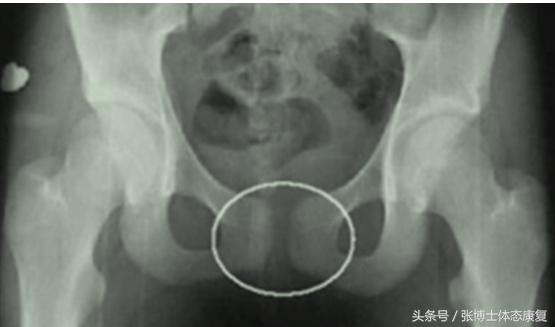

3、影像学检查:正常人耻骨间隙为4~6mm,孕期可增宽2~3mm。影像学X线片见耻骨联合间距离明显增宽,一般认为耻骨联合间隙超过10mm可确诊